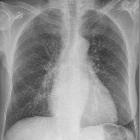

Mammaschatten

fehlender Mammaschatten in der Thoraxaufnahme nach Mastektomie

Röntgen Thorax Normalbefund